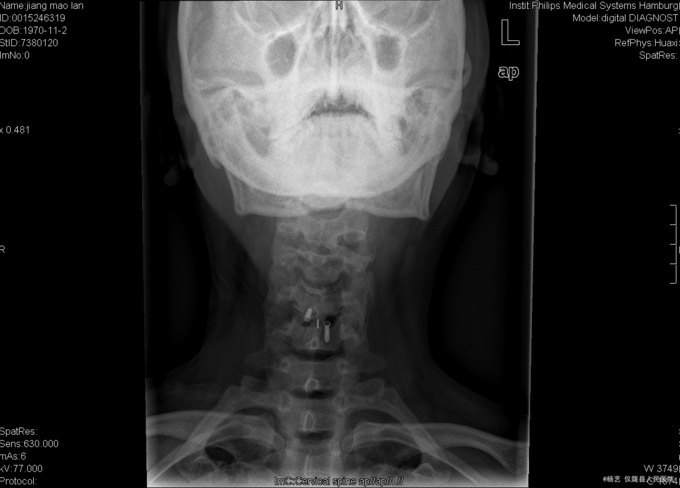

患者蒋茂兰,女,45岁0月,因“头晕伴视物旋转10+月,加重1+月。”入院 10+月前患者无明显诱因出现头晕、头昏;视物旋转,偶伴有呕吐,呕吐为胃内容物;间断发作,发作时持续时间不等,休息后明显缓解。无活动障碍;无肢体麻木、乏力;无行走不稳;无发热、头痛等,1+月前患者上述症状加重,患者于当地医院就诊,治疗未见明显好转。颈椎MRI示:颈5/6椎间盘突出。现患者为求进一步诊治就诊于我院,门诊以“C5/6椎间盘突出症伴脊髓神经不全损害”收入我科。

查体:T:36.9oC,P:78次/分,R:19次/分,BP:109/72mmHg。神志清楚,无病容,皮肤巩膜无黄染,全身浅表淋巴结未见肿大。。颈静脉正常。心界正常,心律齐,各瓣膜区未闻及杂音。胸廓未见异常,双肺叩诊呈清音,双肺呼吸音清,未闻及干湿啰音及胸膜摩擦音。腹部外形正常,全腹柔软,无压痛及反跳痛,腹部未触及包块,肝脏肋下未触及,脾脏肋下未触及,双肾未触及。双下肢无水肿。 专科查体:视:脊柱外观无畸形,活动无异常,无皮肤破溃及窦道形成。触:椎体棘上、椎旁肌无压痛、叩痛,四肢感觉无明显减退,远端血运未见异常。动量:颈部屈伸、左右侧偏活动无明显受限,双上肢耸肩、屈伸肘关节、屈伸腕肌力5级,双手握力5级,双下肢伸髋、屈髋、外展、内收、伸膝、屈膝肌力5级,双足趾背伸肌力5级。双侧肱二、三头肌肌腱反射、膝腱反射、跟腱反射正常引出。双侧Hoffmann氏征阳性,Babinski征阴性,踝阵挛阴性,髌阵挛阴性。 辅助检查:外院MRI示:颈椎退行性变,颈5/6椎间盘突出。垂体区:空泡蝶鞍?

综上初步诊断:1、颈5-6椎间盘突出症伴脊髓神经不全损害;2、白癜风 经前路颈5/6椎间盘切除、椎管及椎间孔减压、椎间融合器植骨融合内固定术。 手术发现:  颈5/6椎间隙变窄,椎间盘髓核干涩,无光泽。颈5/6椎间隙后份少量骨赘生成,椎间盘向后方突出,压迫硬脊膜。术中夹出数块突入椎管内的椎间盘髓核组织及增生骨赘。充分减压后,可见硬脊膜恢复膨隆,双侧神经根松弛,术中未见脑脊液漏。